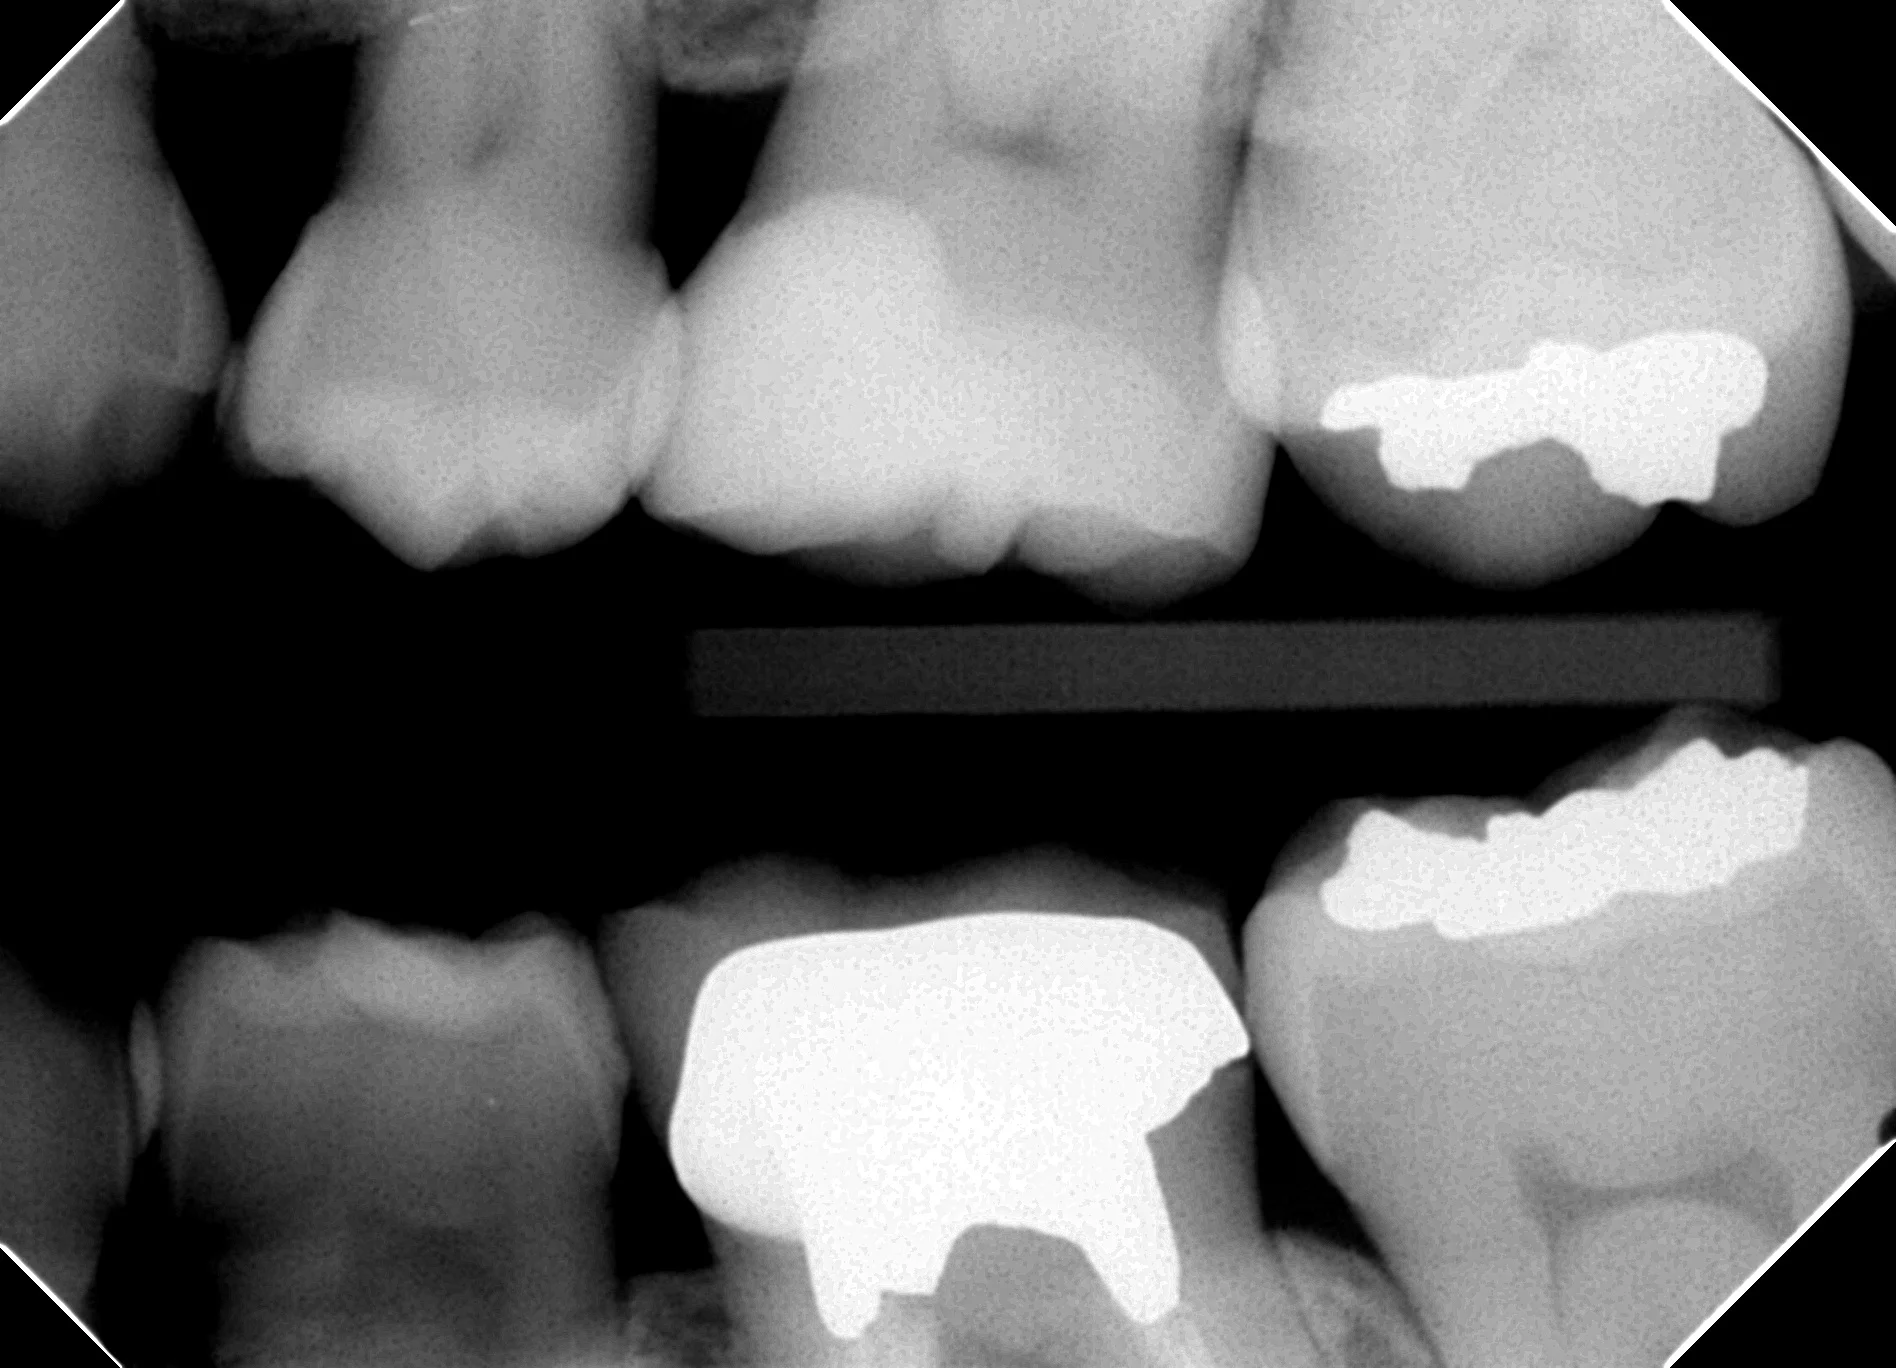

実際の症例写真

実際の症例では、写真のように歯肉縁下およそ2mmからマージンを立ち上げています。

術後2年の時点でも、歯肉の発赤や腫脹は認められず、CR部へのプラーク付着も確認されません。

一般にコンポジットレジンはプラークが付きやすいと言われますが、歯肉に接する領域にGiomerを選択的に用いることで、良好な経過を維持できるケースを多く経験しています。